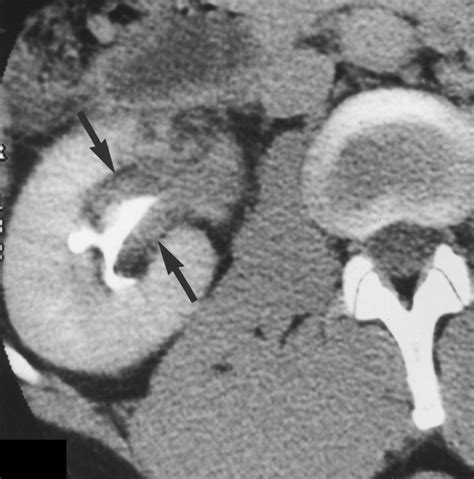

• Imaging Studies: An ultrasound, CT scan, or MRI can provide a clear view of the organs in the right flank, identifying stones, cysts, or inflammation.